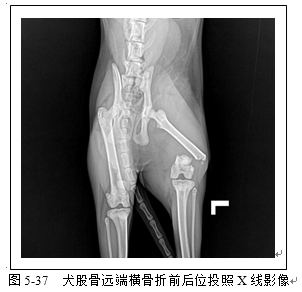

四肢骨骼X线评估常用于骨折检查(图5-36、5-37、5-38、5-39)以及关节脱位(5-40)检查。